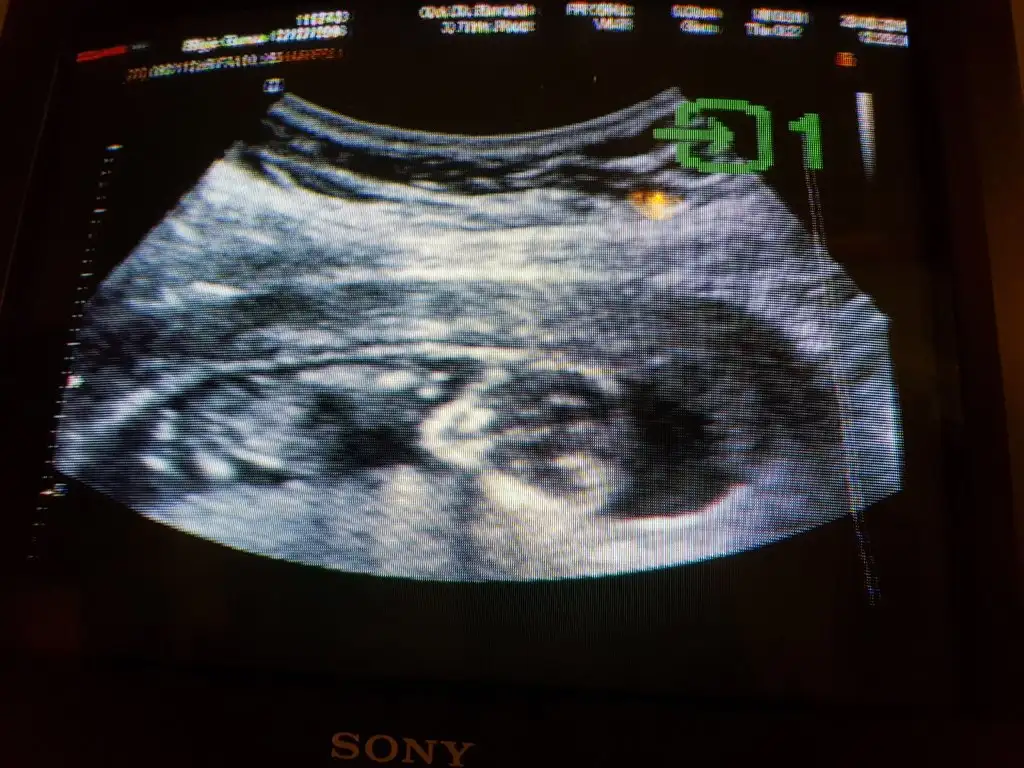

Nub yöntemine göre cinsiyet tahmini

Nub çizgisini bariz görüyorum.popoya paralel.yani bebeğin kız.nub çizgisi bebeğin cinsiyetinin oluşmadan önceki aşaması.nub cizgisi dik ise erkek,paralel ise kız olur.